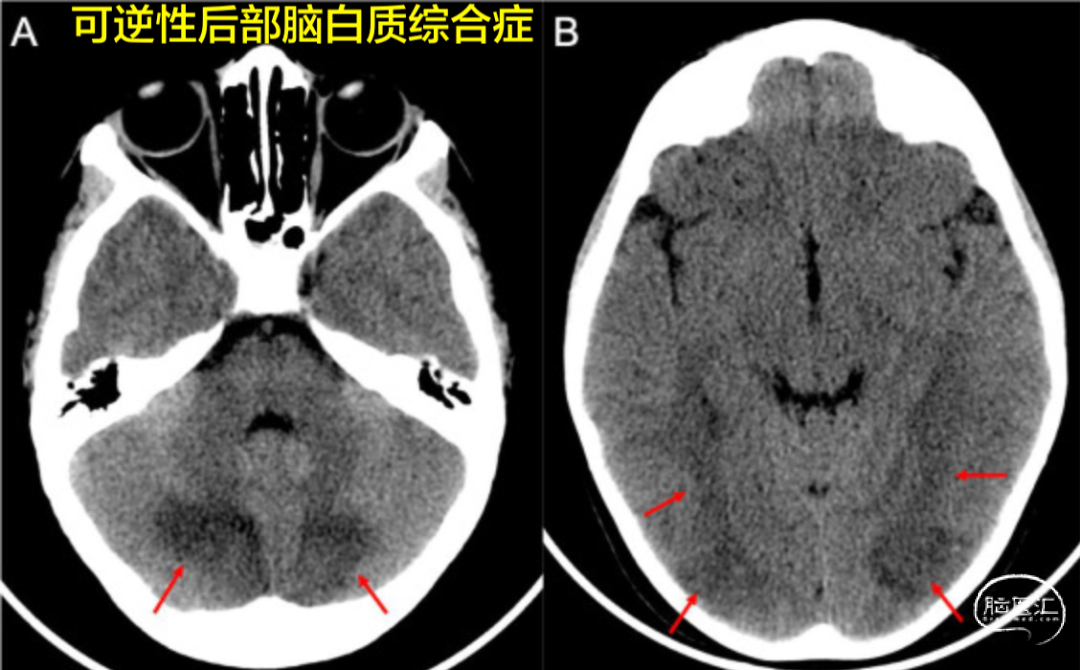

霹雳性头痛的严重原因,可能有多种,包括:蛛血、其他颅内出血、可逆性脑血管收缩综合征(RCVS)、可逆性后部脑病综合征(PRES)、高血压危象、脑静脉窦血栓形成、颈部动脉夹层,或脑梗死。

如果通过评估排除蛛血后,仍不确定的病因,建议进行额外的检查,如增强MRI、磁共振血管造影(MRA)、和磁共振静脉造影(MRV)。